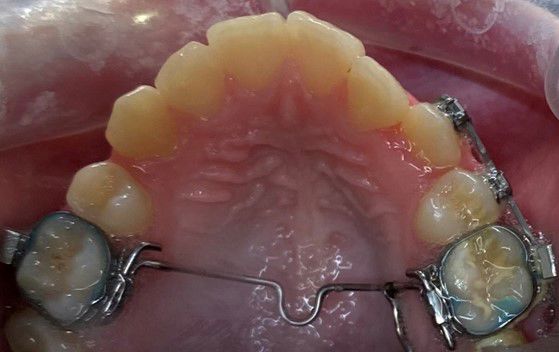

Sidder på tandbånd og ligger langs ganen, for at holde eller ændre på 6-års tænderne i overkæben. Desuden kan den holde eller øge tandbuens bredde.